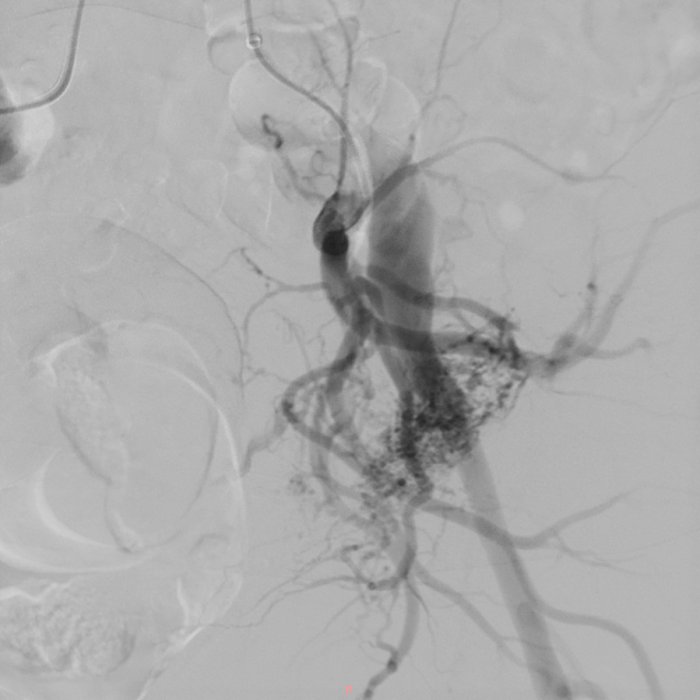

山重水复疑无路,柳暗花明又一村。面对诊断困境,血管外科团队决定启用诊断血管疾病的“金标准”动脉造影。当造影剂经由动脉注入,清晰的动态图像实时呈现时,患者的病因终于水落石出,其左髂内动脉多个分支存在动静脉畸形,造影清晰地显示了畸形血管团以及静脉血经髂静脉反向回流的情况。

3 左髂内动脉多个分支动脉可见动静脉畸形 00_00_00-00_00_30.gif

动脉造影结果显示,左髂内动脉多个分支可见动静脉畸形

至此,困扰朱奶奶多年的病因终于真相大白,她患上的是左下肢动静脉畸形合并髂静脉压迫综合征。这是一种临床上较为罕见的病例,其严重的下肢肿胀和复杂的影像学表现,均与这一诊断高度吻合。